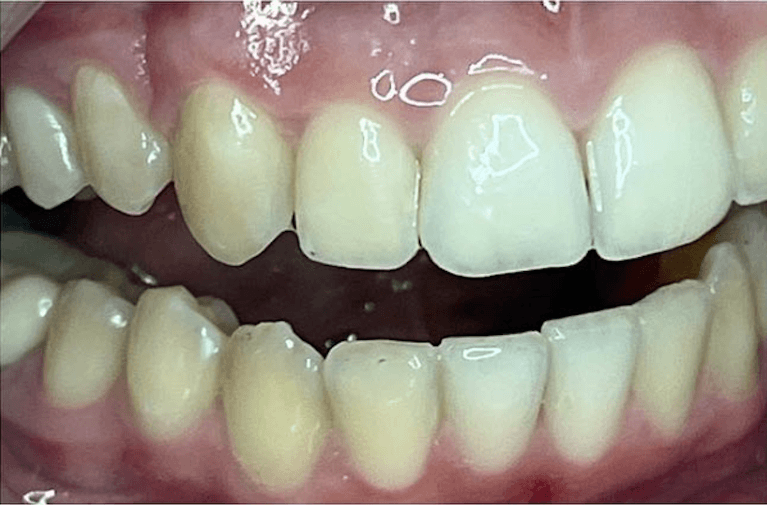

White spot treatment with Icon and mild spacing correction with Invisalign(5weeks only)